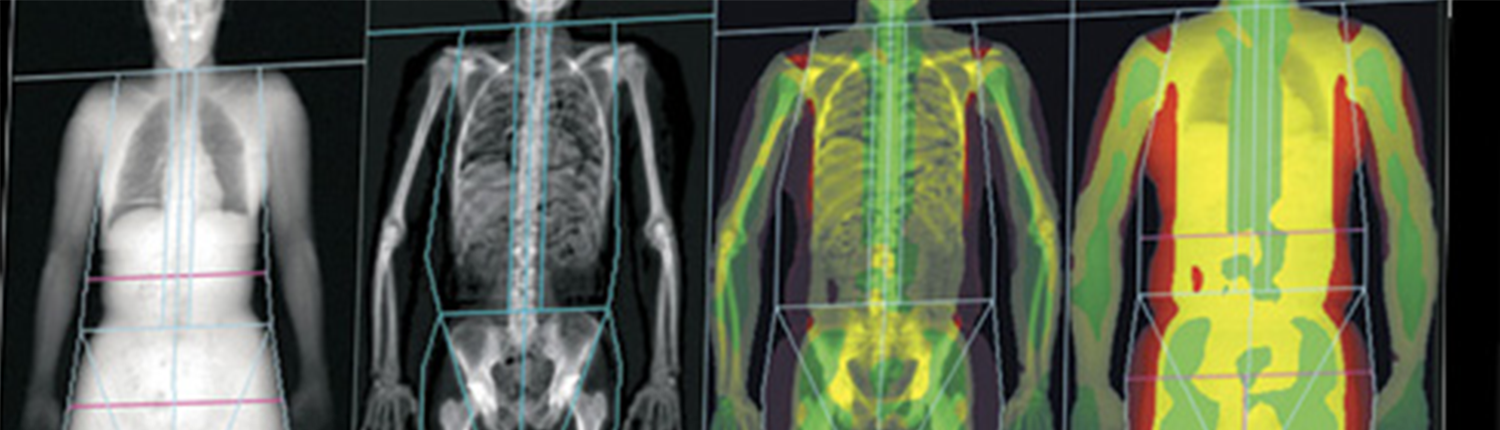

La Unitat de Metabolisme Mineral i Ossi és un servei especialitzat en el diagnòstic, tractament i seguiment de trastorns relacionats amb el metabolisme dels minerals i la salut òssia. Aquesta unitat aborda principalment patologies com l’osteoporosi, el raquitisme, l’osteomalàcia, i altres malalties que afecten la densitat i estructura òssia, així com desequilibris en els nivells de calci, fòsfor i vitamina D. També tracta condicions metabòliques relacionades amb les glàndules paratiroides i altres disfuncions endocrines que poden comprometre la salut dels ossos. L’objectiu és prevenir fractures i mantenir la qualitat de vida del pacient.